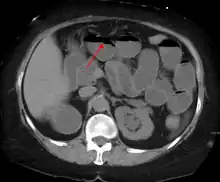

Contrast enema or small bowel series or CT scan can be used to define the level of obstruction, whether the obstruction is partial or complete, and to help define the cause of the obstruction. The appearance of water-soluble contrast in the cecum on an abdominal radiograph within 24 hours of it being given by mouth predicts resolution of an adhesive small bowel obstruction with sensitivity of 97% and specificity of 96%.[18]